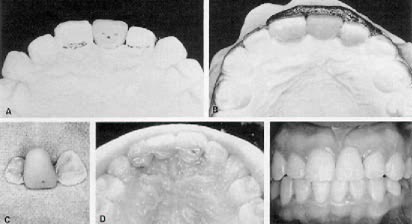

Fig. 4 A. 15-year-old patient with congenitally missing mandibular incisors. B. Wire with retentive loops bonded to lingual surfaces of canine abutments. C. Custom-processed acrylic teeth on model. D. Bridge removed from model, and excess composite trimmed away. E,F. Bridge bonded in place.

Fig. 5 A. Patient with anterior crowding requiring extraction of mandibular right central incisor. B. Cantilevered, custom-processed acrylic replacement tooth on model. C. Beginning of treatment with pontic bonded in place. Pontic is reduced as space closes. D. Completed case.